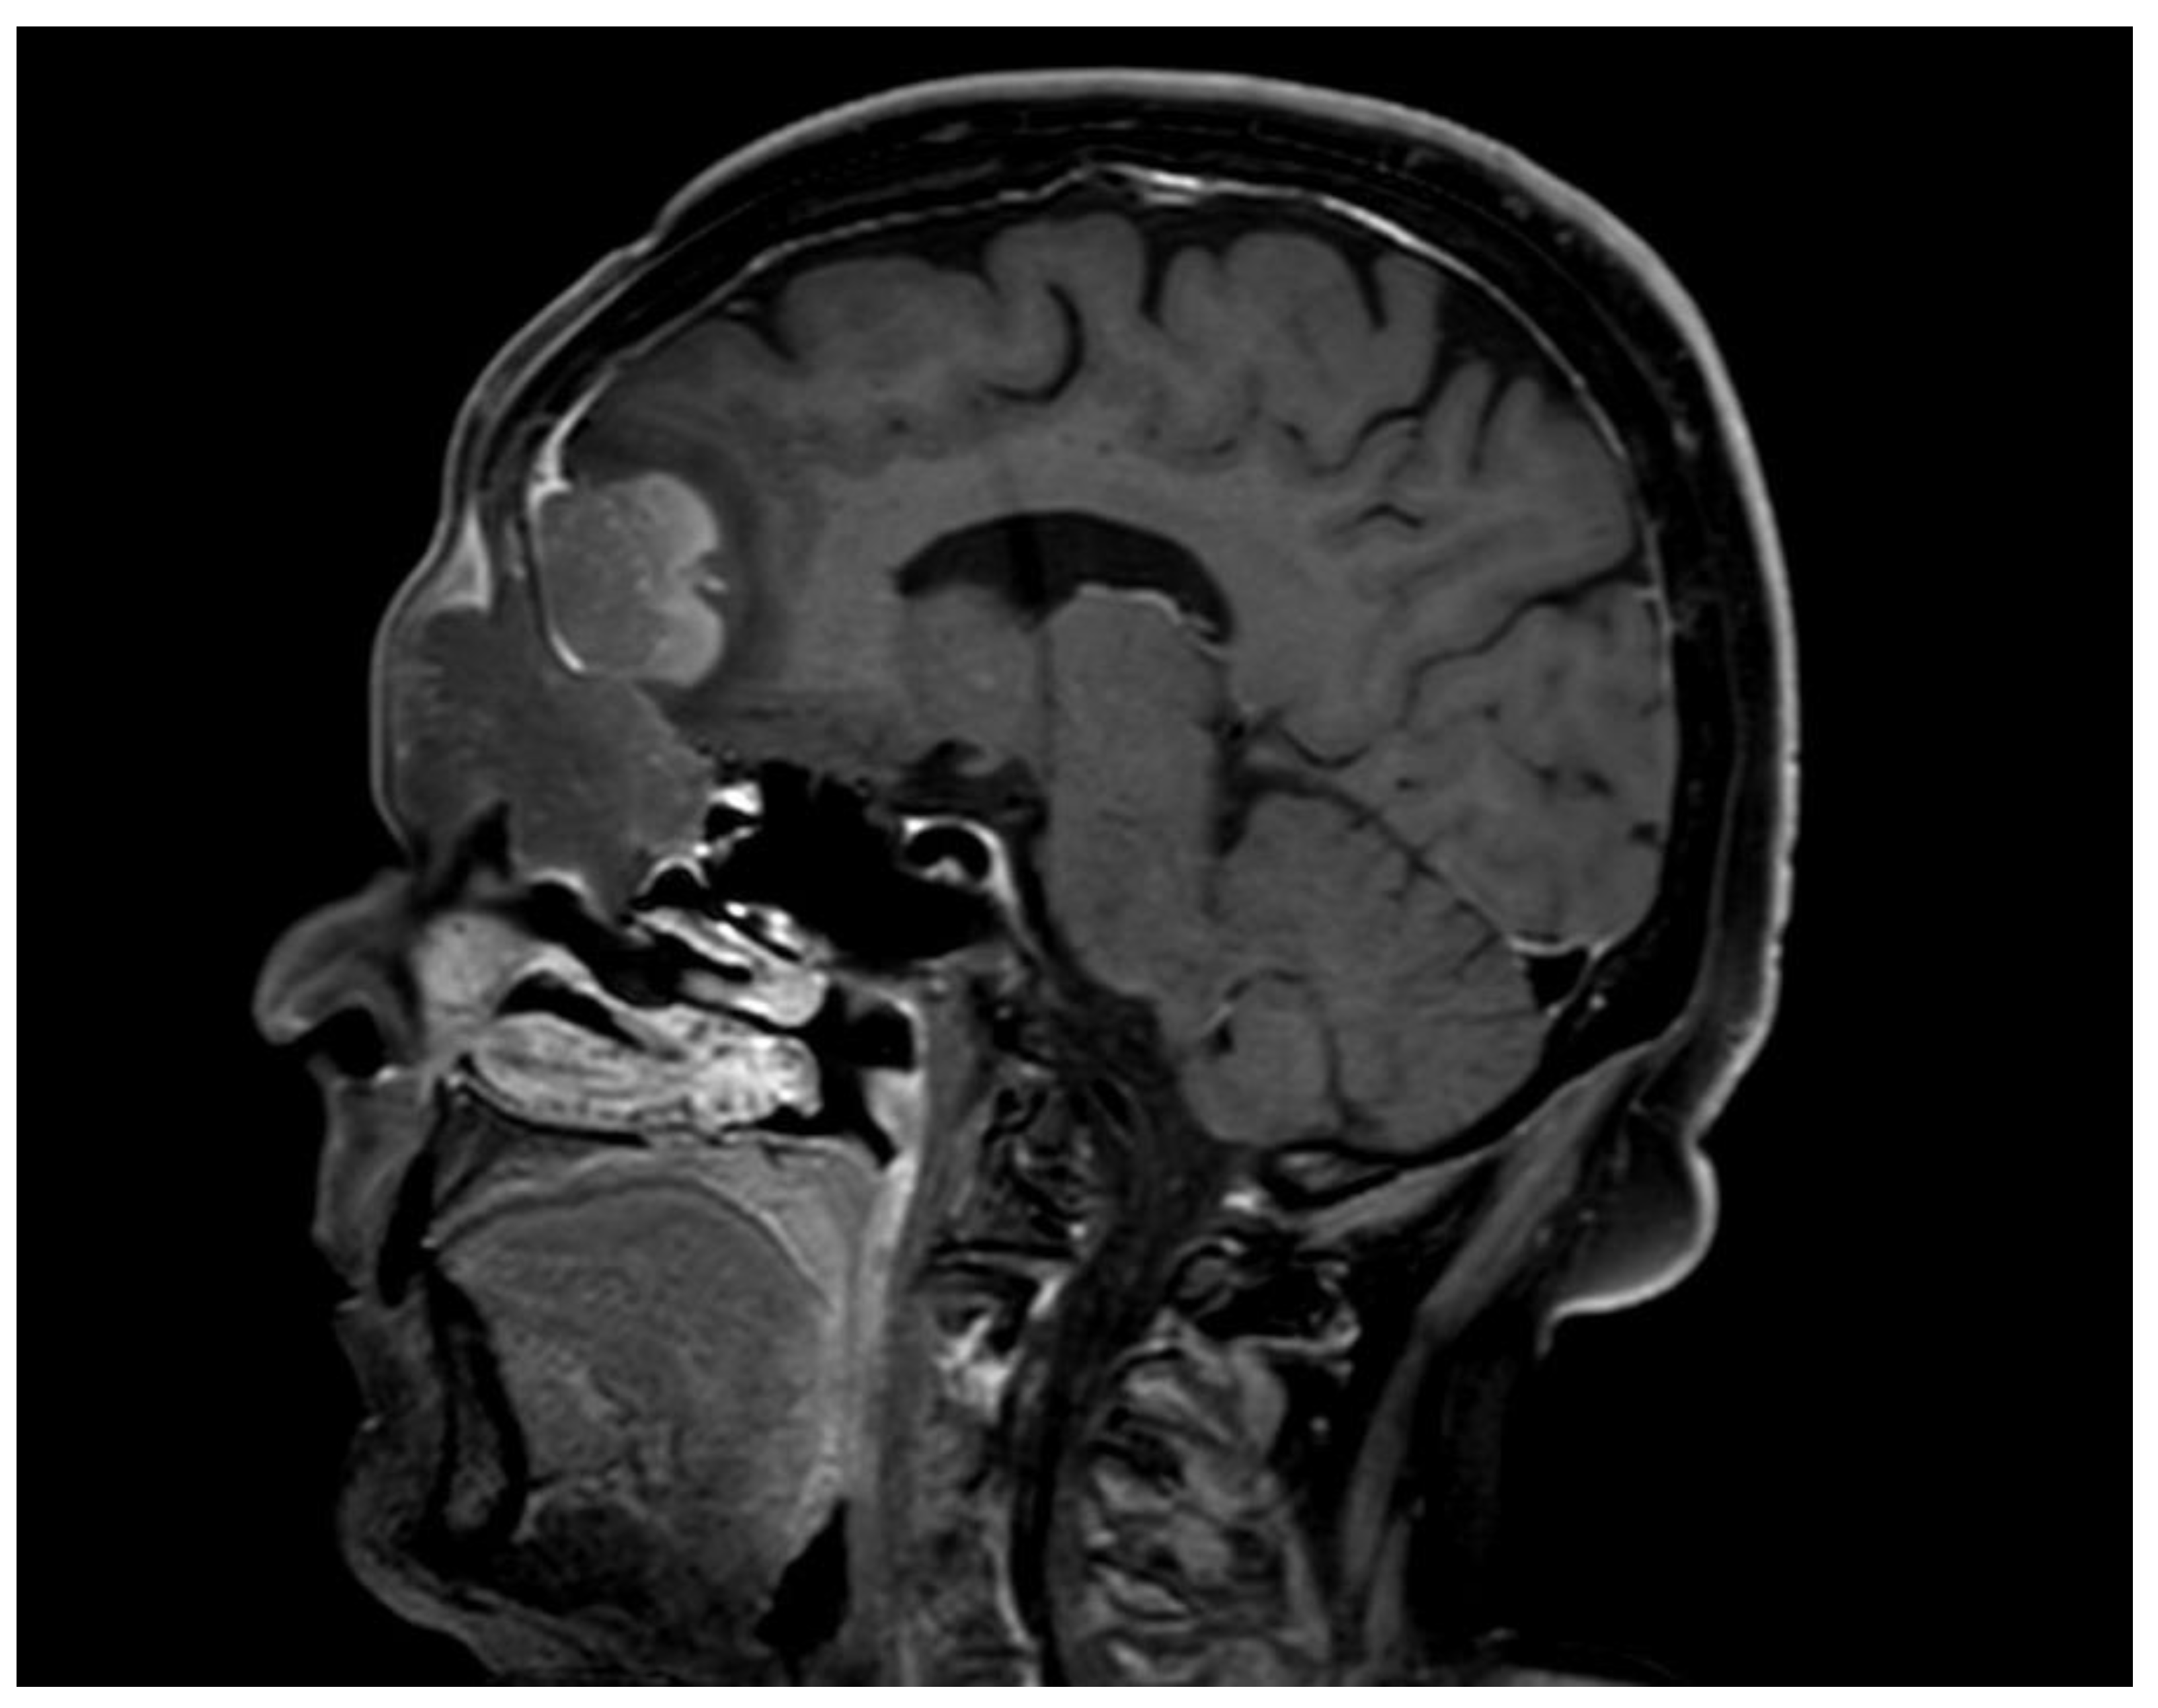

2. Case Report